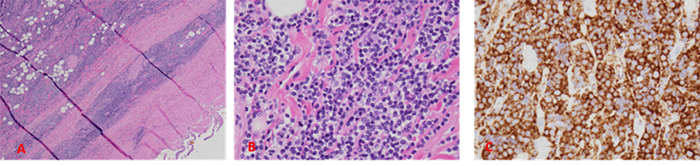

Bone marrow biopsy, performed as part of staging workup, revealed hypercellular marrow with reduced trilineage hematopoiesis and atypical B-cell infiltrates (Figure 2). Positron emission tomography (PET)/computed tomography (CT) scan identified mesenteric and external iliac lymphadenopathy along with focal bony involvement (Figure 3). The presence of atypical B-cell infiltrates in the bone marrow confirmed stage IV lymphoma by the Lugano classification.7

Figure 3. PET-CT Scan Findings. Published with Permission

A (coronal and sagittal views): Heterogeneous and focal fluorodeoxyglucose (FDG) uptake within the spinal column, indicating bony disease involvement (white arrows). B (lower axial view): Lymphadenopathy (yellow arrow) in the mesenteric and external iliac regions alongside bony involvement of the pelvic bones (white arrows)